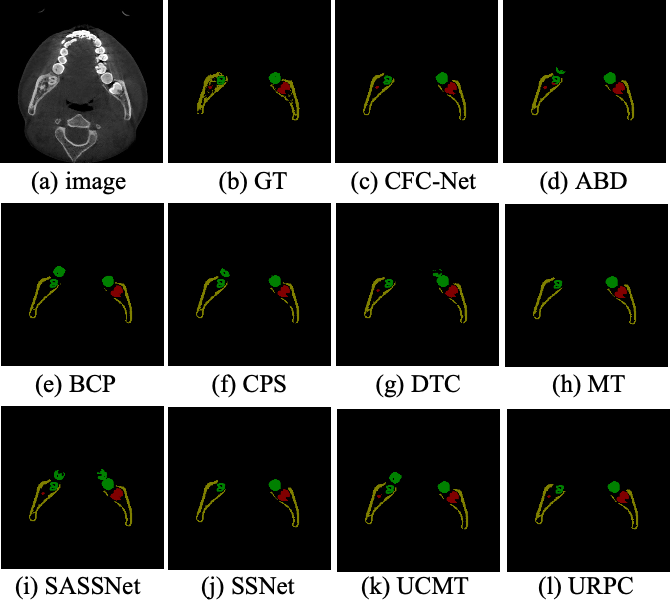

5.3.1 Results on the FMRC-2025

As shown in Fig. 5, the qualitative comparisons of CFC-Net with other SOTA SSL medical image segmentation methods are presented. It can be observed that CFC-Net closely approximates the ground truth (b), achieving accurate and complete segmentation, even in the fine, intricate regions deep within the RC. In contrast, other networks exhibit omissions in identifying these subtle structures. This underscores the critical importance of UCF-Mix in preserving the integrity of segmentation labels. Table 1 presents the quantitative results of the experiments, we conducted experiments using 10% and 20% of the labeled data, respectively. The results show that CFC-Net outperforms existing SOTA methods across most evaluation metrics. Notably, compared to recent SOTA SSL medical segmentation methods that utilize mix-up mechanisms, CFC-Net exhibits advantages in the RC segmentation task.